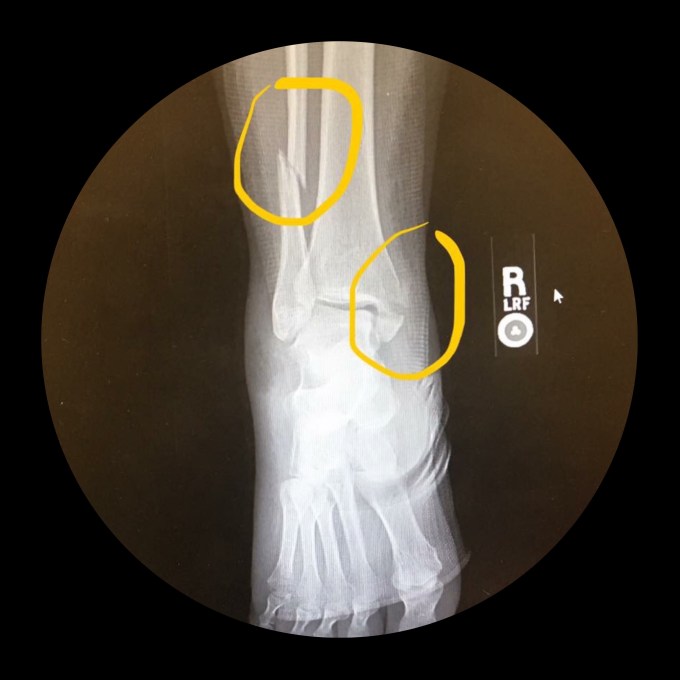

This is my broken leg.

I am not sure if you can see both sides, but the x-ray reveals a broken fibula and tibia. The more visible break in the top of the photo and also my ankle.